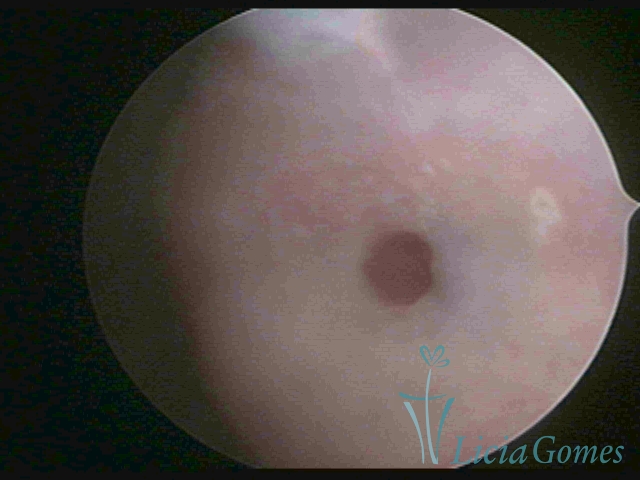

Third part or upper section

Presents the mucosa with a smooth, poorly vascularized surface, to the internal orifice